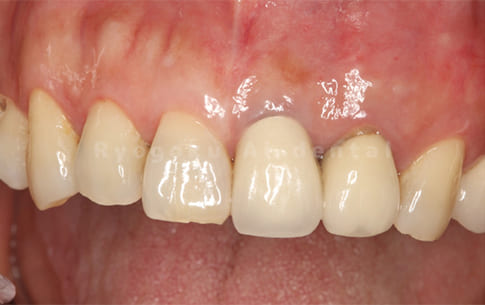

Case07

-

- 原因

- 右下6番歯根破折

- 治療内容

- インプラント治療

- 治療費用

- 約600,000円

右下の腫れが治らないとの事でご来院された患者様です。歯が割れていたため、抜歯を行い、骨に代わるお薬を入れ、インプラントを埋入致しました。経過良好で大変満足していただけました。

<リスク・副作用>

治療後、痛みや違和感、出血、腫れなどが出る事があります。喫煙者、糖尿病などの方の場合、歯が生着しない場合があります。